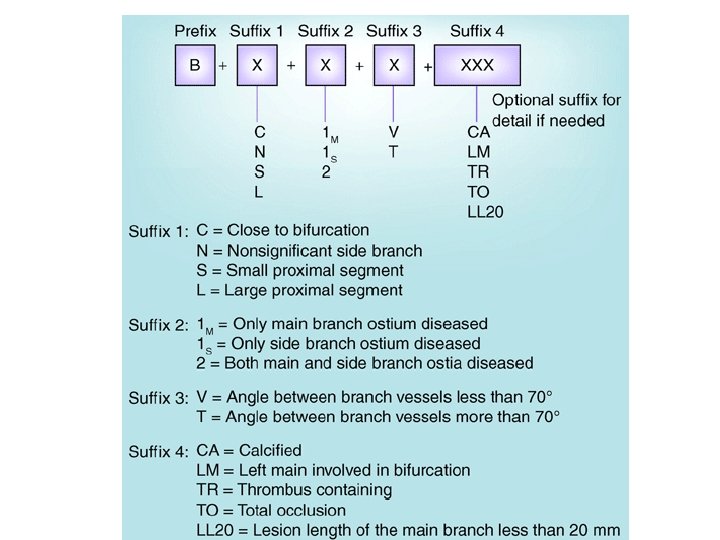

Classification • • Sanborn Lefevre Safian Duke • MEDINA • MOVAHED